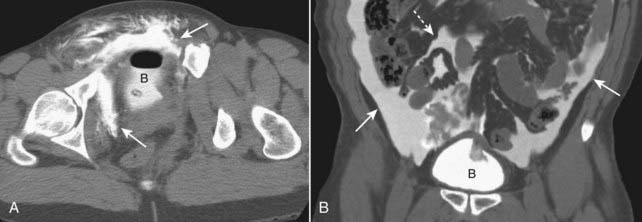

image

Figure 17-9 Renal trauma, two different patients.

A, Coronal-reformatted, contrast-enhanced CT scan shows a low-attenuation linear defect representing a renal laceration (solid black arrow) and a subcapsular hematoma (solid white arrow). B, Axial CT scan on another patient also shows a renal laceration (solid black arrow) and a perinephric hematoma (dotted black arrow).

Figure 17-10 Tear of proximal ureter.

There is a tear of the ureter at the level of the left ureteropelvic junction demonstrated by extraluminal contrast (solid white arrow) representing contrast-containing urine that is leaking from the collecting system.